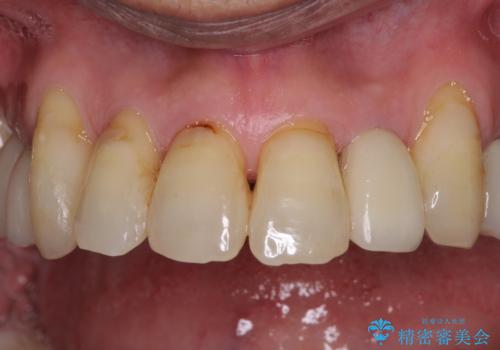

- 前歯がのデコボコや、奥歯に咬んだときに痛みがあるとのことで来院された患者様です。

全体的に問題が多く、全てをしっかりと治療したいとのことでした。

全体的に中等度の歯周病と診断されたため、歯周外科処置やインプラントによる咬合回復から進めて行き、矯正治療による歯列改善を行った後にオールセラミッククラウンにて補綴することとしました。

初診来院時には矯正治療を行うことは想像していなかったようで、治療後には咬みやすさだけでなく、前歯が大変審美的に仕上がり、患者様には大変満足していただきました。